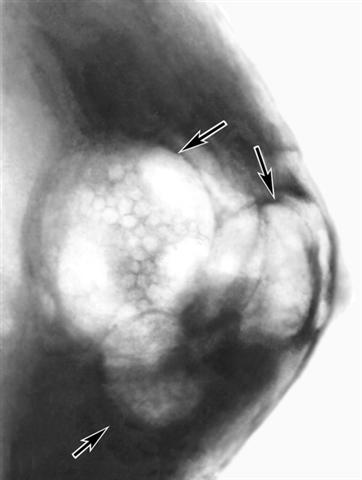

Рис. б). Пневмомаммограмма при мастопатии (стрелками указаны заполненные газом крупные кистозные образования с полициклическими контурами).